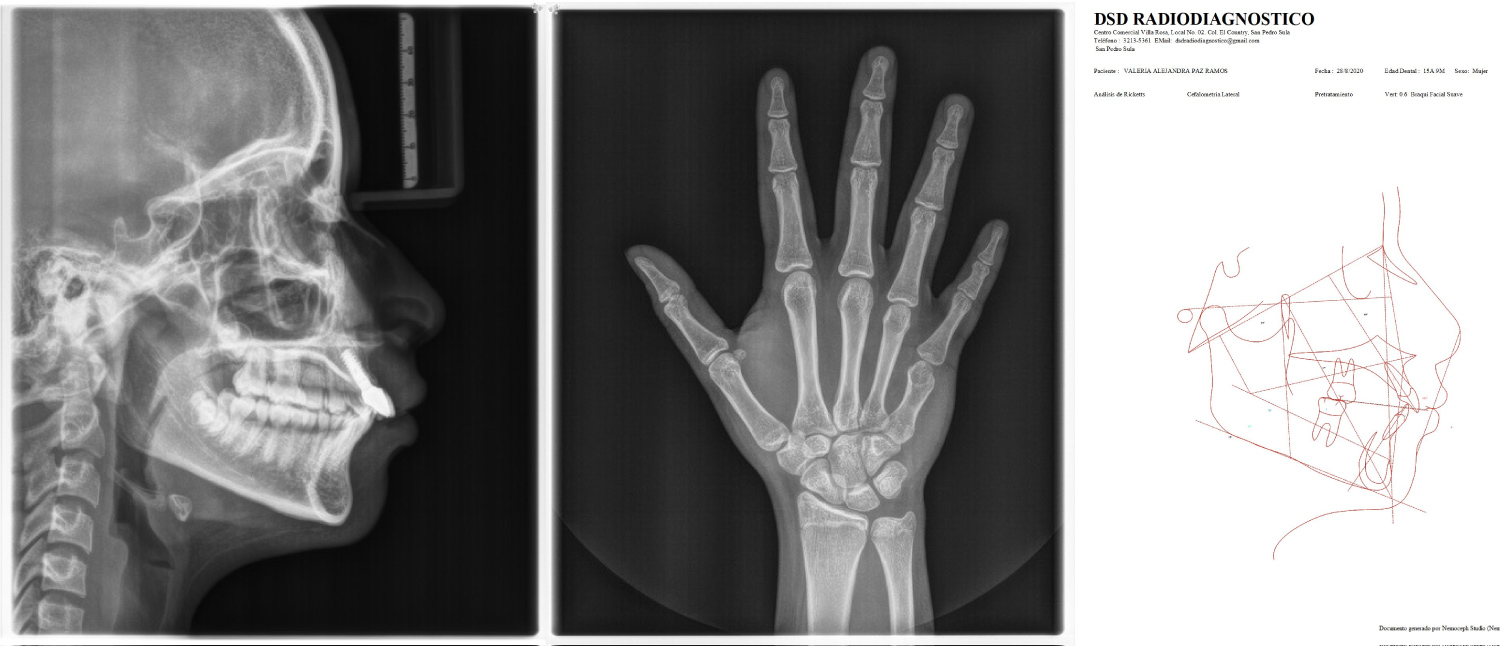

Additionally, cephalometric analysis and hand/wrist radiographs were analyzed to identify the physical development stage of the patient and correlate them to the chronological age. (Once skeletal maturity was assessed and appropriate surgical and prosthetic treatment plan was outlined, surgical procedure could be performed) (Figure 3).

Figure 3: (A) Lateral radiograph; (B) Hand and wrist radiography; (C) Cephalometric analysis. View Figure 3

Skeletal growth status can be appraised fairly accurately by comparing a conventional radiograph of the hand and wrist against a standardized atlas of hand and wrist bone development. Hand wrist radiograph indicators can be used to place a patient in the general area of the growth curve. Capping of the middle phalanges of the third finger (MP3cap) usually occurs after maximum growth velocity is completed and indicates a deceleration in the pubertal growth spurt. Once pubertal growth is completed, consideration of implant placement can begin. However, some risks still exist. When epiphysis of the radius fuses and forms a bony union with the diaphysis, the adult level of skeletal growth has been attained and no further increase in structural height can be expected [10].